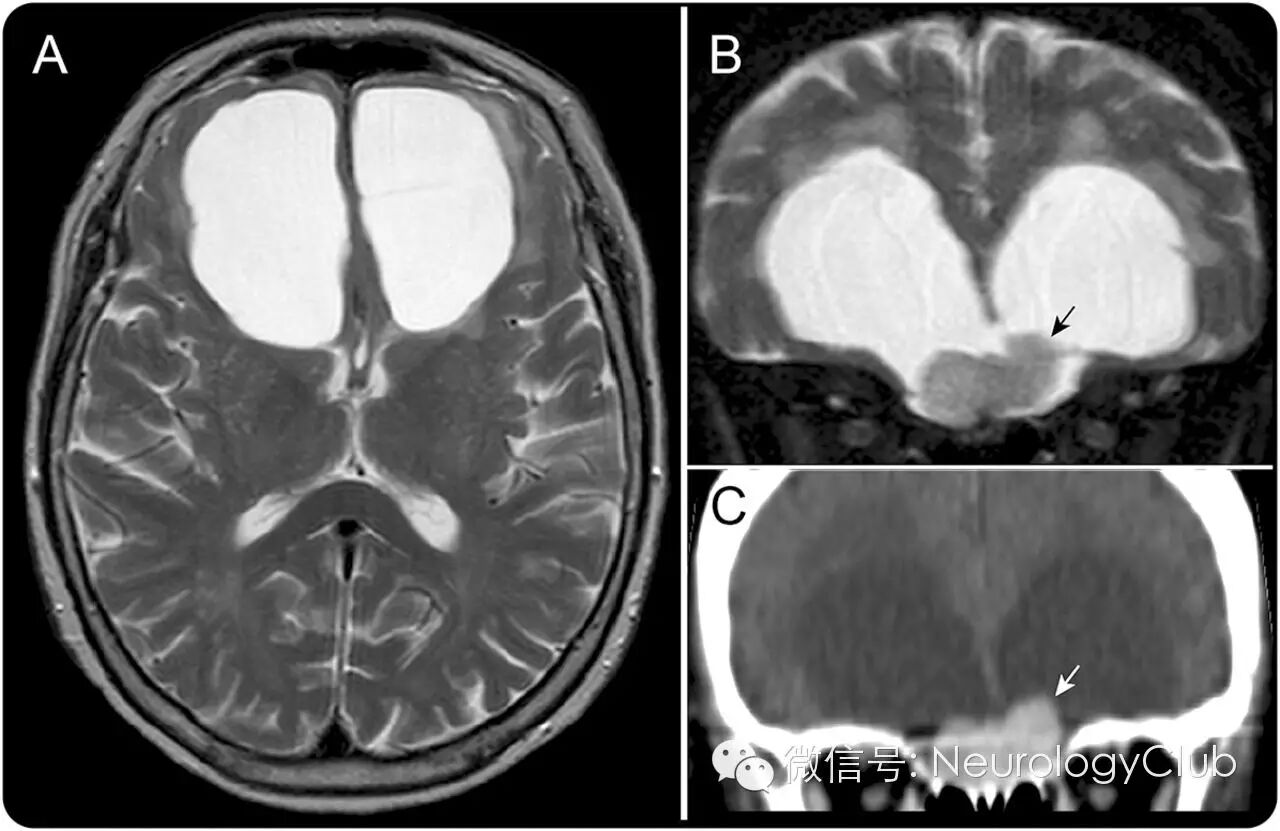

73岁女性,表现为进行性冷漠,健忘和步态障碍6月。神经系统查体提示注意力不集中,记忆缺陷和宽基步态。因患者钆过敏,故只能行非强化磁共振检查。MRI和增强CT提示双侧额叶对称性囊肿(图1A)以及前颅底结节状病灶(图1B和C)。手术证实为鸡冠部来源的脑膜瘤(图2A)。术后患者症状改善,囊肿缩小(图2B)。

(图2:[A]双额经路术中可见囊壁[箭头]和脑膜瘤[箭],起源于鸡冠部硬脑膜[开放箭头]。虚线为中线;[B]术后4月的T2WI证实囊肿缩小)